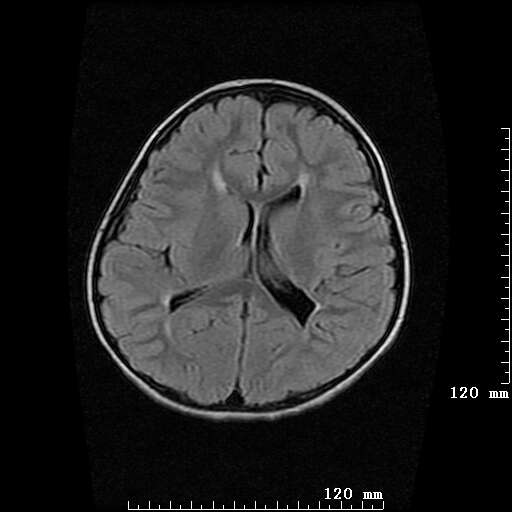

女,7岁,三岁才说话、走路。现智力尚可,走路不稳。临床怀疑大脑发育不全。

侧脑室周围白质软化症。

侧脑室周围白质数量减少,侧脑室不对称性扩大,左侧侧脑室后角呈方形改变,脑沟加深,结合临床考虑脑室周围白质软化症(pvl)。期待结果!

只看出灰质异位